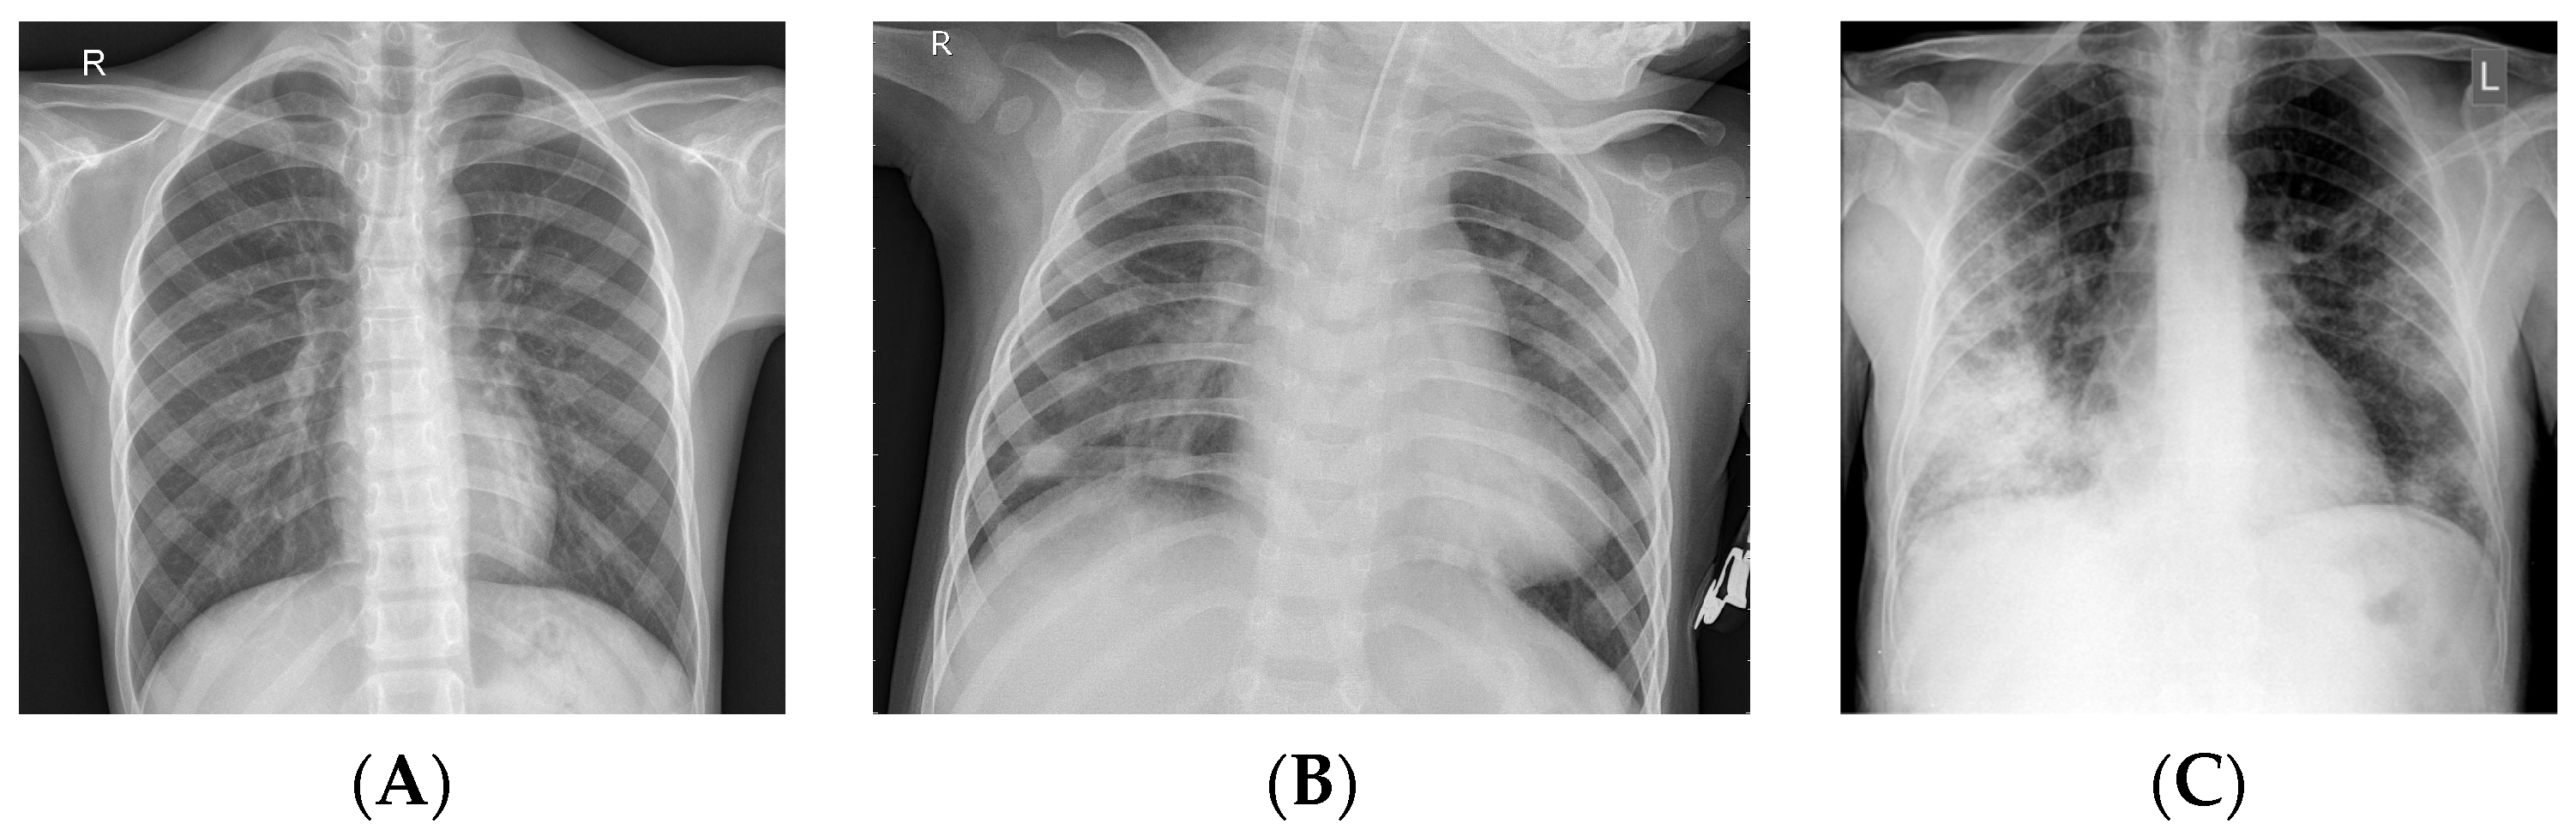

3.1. Dataset

4.1. Generating the DCGAN Image

4.2. Classification Results